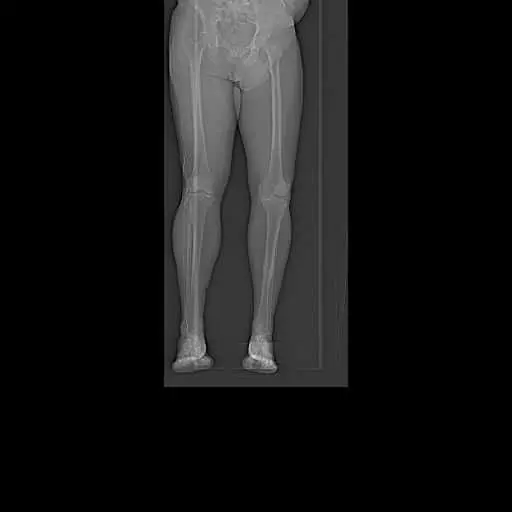

Preoperative Scanogram images obtained from CT tomography

Patient detailed anatomy and biomechanics axis were obtained from a preoperative CT scan. The data obtained was used to construct custom implants. The custom implants were unique for the patient’s anatomy. Disposable 3D constructed jigs were made for accurate bone cuts. A preoperative plan was formed to aid the surgeon in the operation.